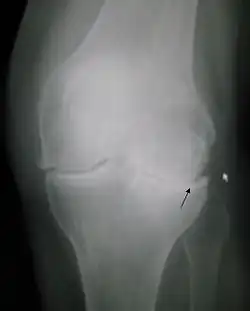

Si se utilizan elementos clínicos complementados con una radiografía basta con que ésta presente osteofítos, es decir que presente crecimiento excesivo de tejido óseo alrededor o dentro de la articulación en cuestión y que se presente al menos uno de los criterios siguientes:

Para reconocer una artrosis de rodilla gracias a una radiografía, se tiene que observar un espacio articular reducido y la presencia de osteofitos.[3]

De acuerdo a la escala de Kellgren y Lawrence se puede estudiar la progresión de la artrosis, estableciendo así distintos grados según diferentes criterios como lo son la presencia de osteofitos, los cambios en el hueso subcondral, entre otros.